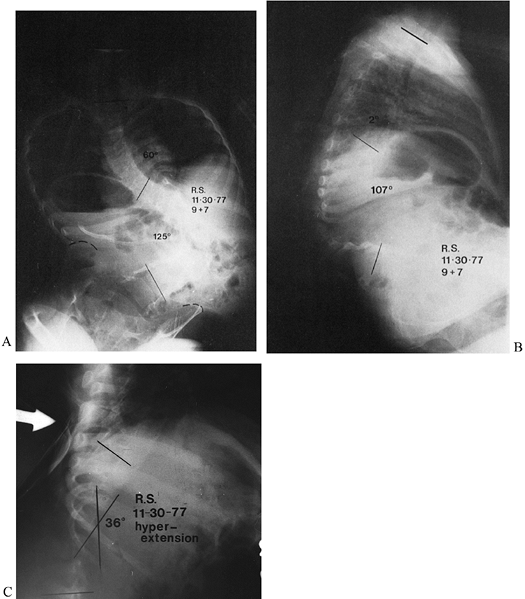

In rotational kyphosis, however, the vertebral bodies are rotated out

of the sagittal plane, as is commonly seen in paralytic curvatures and

kyphosis secondary to neurofibromatosis (Fig. 161.2).

Figure 161.2. A: A 9-year-old child has a paralytic right thoracolumbar scoliosis of 125°. B: In addition to the paralytic scoliosis, a rotational thoracolumbar kyphosis of 107° is present. C: The rotational kyphosis corrects to 36° on supine hyperextension (a flexible kyphosis).